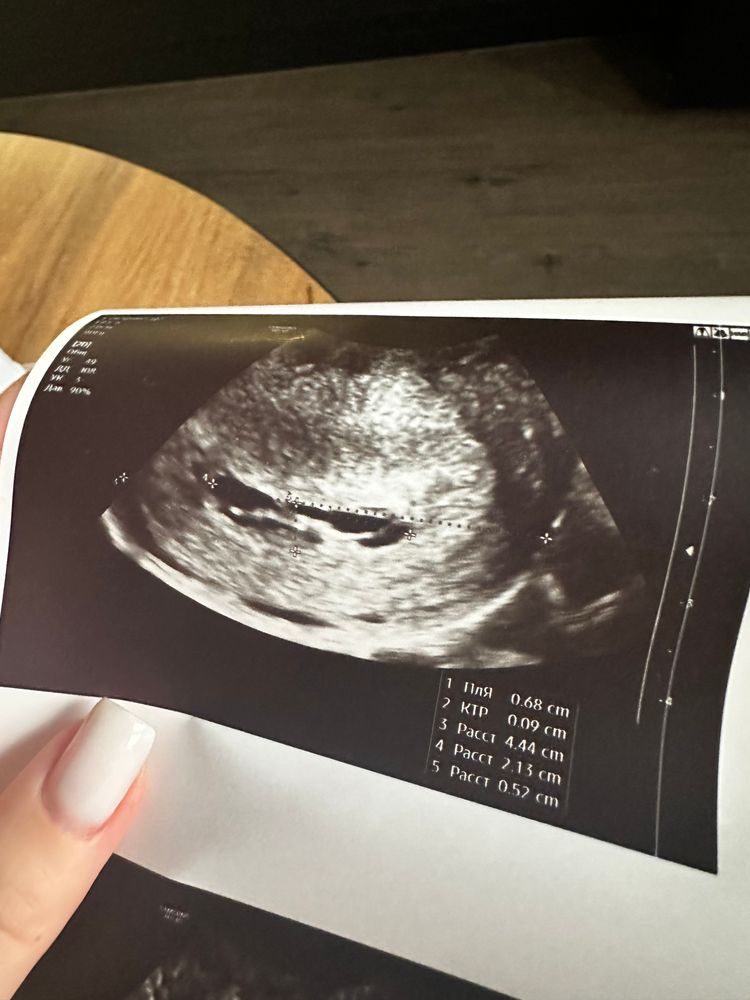

Сходила на второе узи к другому узисту,тоже не понимает,что происходит,в заключении про плодное яйцо вообще ничего не пишет,говорит,что скорее всего не развивающаяся,потом говорит про возможность двойни😣ох уж эта неопределенность(Говорит,я могу предположить,что это начало развития эмбриона(на фото ниже),но это прямо совсем сомнительно,сказала😣

Она на всех снимках замерила ктр как бы))) значит, есть жм, есть уже даже эмбриончик, просто маленький совсем. На первом снимке не пойман жм, но четко виден эмбрион.